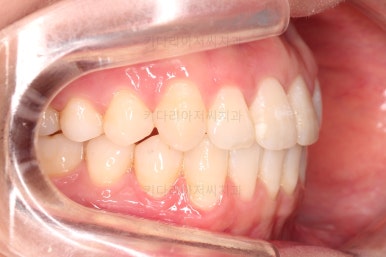

부산교정잘하는치과 초진 시 입안의 모습입ㄴ디ㅏ.

맞물림은 크게 나쁜 편은 아니었고요.

앞니 쪽이 위아래가 다 삐뚤고, 위에 작은 앞니 하나가 거꾸로 물리는 상태였습니다.

거꾸로 물리는 상황에서 특히 아래 앞니는 점점 잇몸이 꺼지는 증상이 생기면서 장기적인 치아의 수명에 영향을 주게 됩니다.